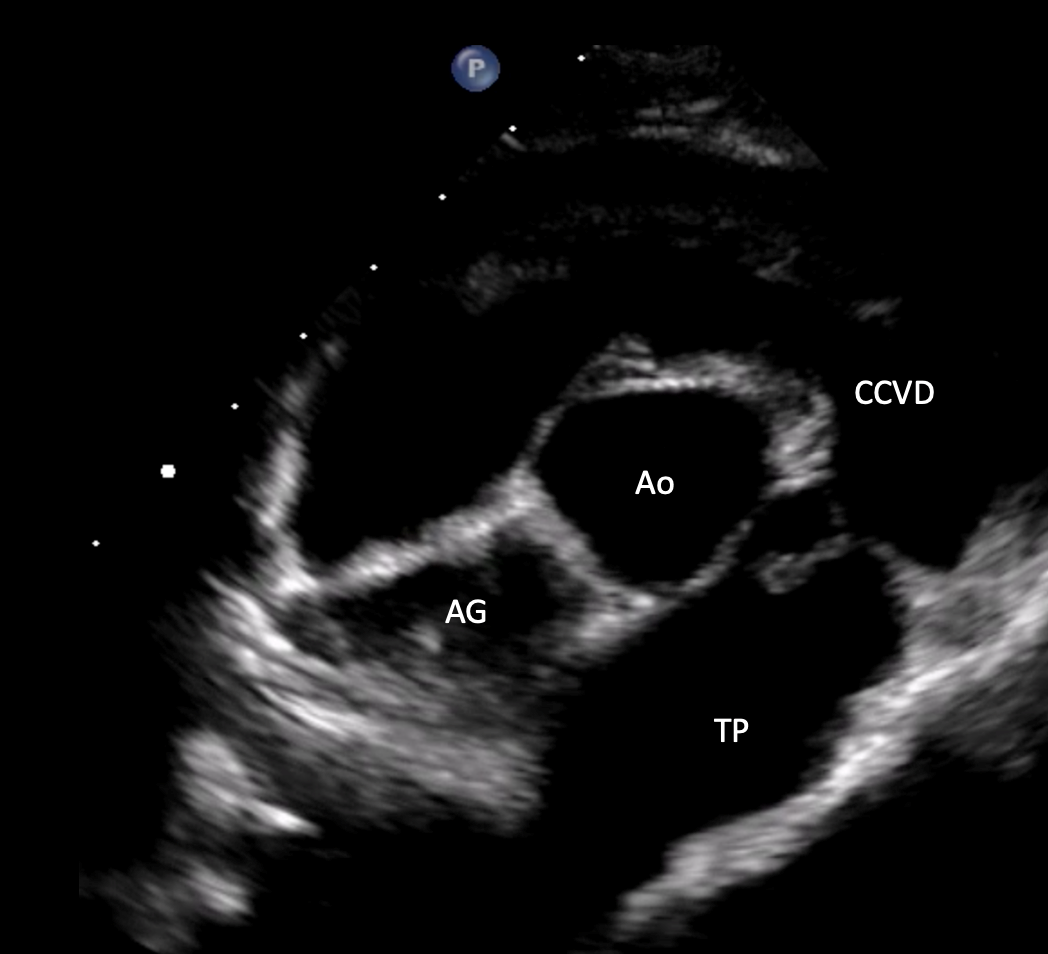

• Utiliser les anomalies observées en modes 2D, TM et Doppler pour classifier et graduer les cardiopathies acquises.

• Étude de cas interactifs à partir d’images fixes et de vidéos en échographie cardiaque (modes 2D, TM, Doppler).

• Objectif : adopter une démarche systématique pour repérer, décrire et interpréter les lésions échographiques, en vue d’établir un diagnostic différentiel pertinent.

• Principes de l’échocardiographie 2D, TM et Doppler appliqués aux cardiopathies acquises.